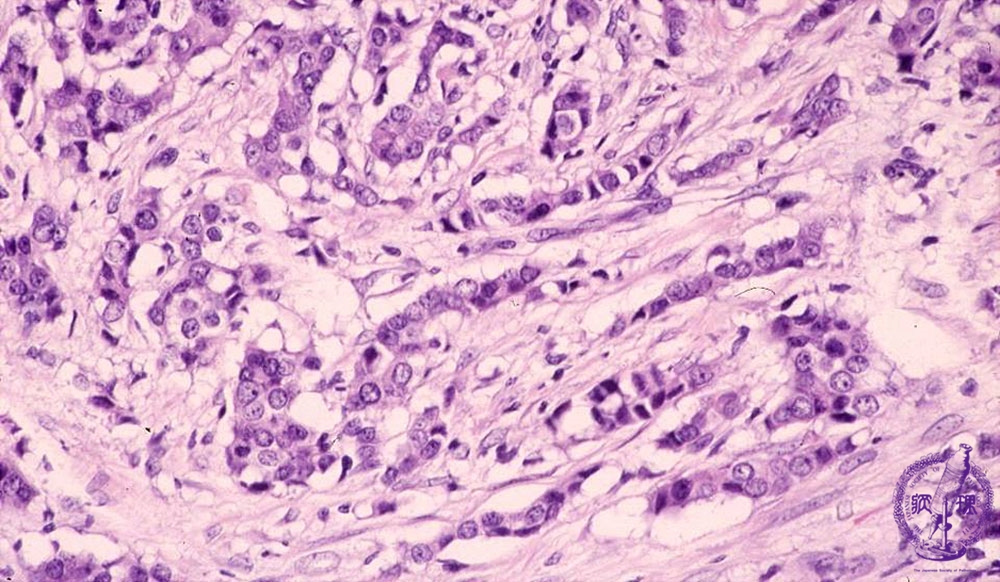

- 14.Breast

- š(6)Invasive ductal carcinoma(Scirrhous carcinoma)

Microscopic image(HE stain, high power view):Marked tumor infiltration has evoked reactive stromal fibrosis. This cancer termed gscirrhoush cancer and is classified as a poorly differentiated ductal carcinoma. Infilatration of small nests and cords of carcinoma cells is also observed.